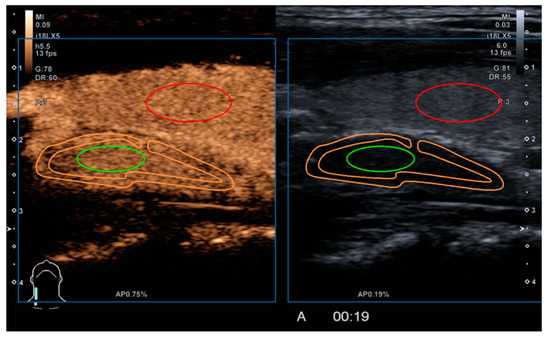

2.2. Study Methodology

2.3. Qualitative Parameters

2.4. Quantitative Parameters